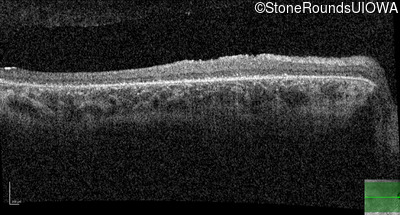

Optical Coherence Tomography - Right - 20/100 -1 sc

Exemplar / OCT Stack